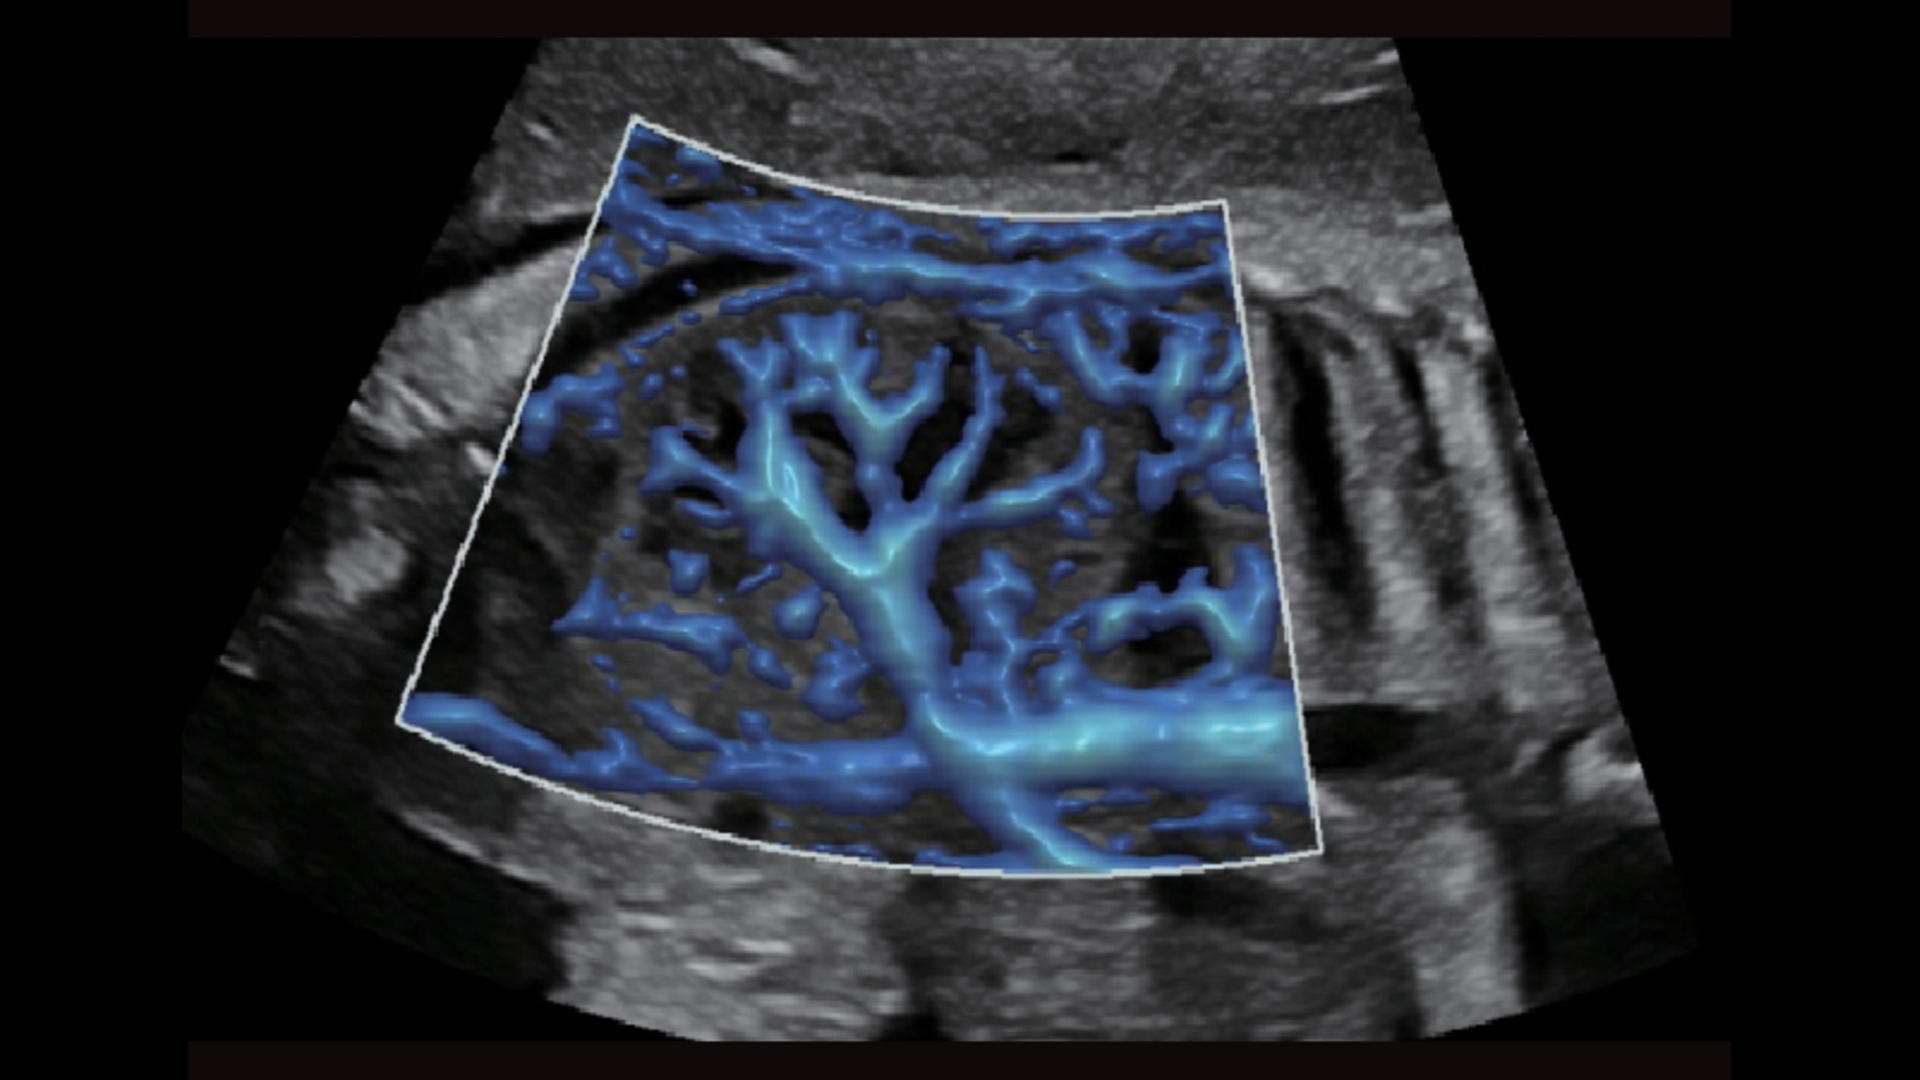

UMA (Ultra-Micro Angiography)

The innovative technology breaks the bottlenecks of traditional Doppler imaging. With ultra-high spatial resolution and flow sensitivity, it allows detecting super-subtle and super-slow flow perfusions, thereby extending the clinical application of qualitative and quantitative ultrasound evaluation in fetal brain, kidney, placenta, endometrium, ovary, etc.

UMA - fetus renal flow